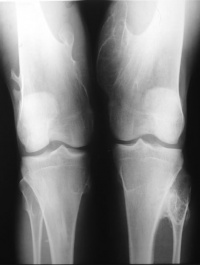

多发性骨软骨瘤表现为干骺端增粗,皮质变薄,肿瘤外形不一,常出现患骨关节畸形,当肿瘤恶变时,其表面的软骨部分迅速长大,当有大量钙化时,则X线表现明显。

主要有两种学说Virchow于1891年提出骺板细胞分离学说,认为骺板的软骨细胞从骺板分离,旋转90°后沿长骨长轴相垂直的方向生长,即横向生长形成肿瘤。另一学说认为起源于骨膜的软骨细胞巢不断增殖骨化所形的肿瘤。后来D.Ambrosia和Ferguson通过骺板软骨细胞移植,成功地产生了骨软骨瘤模型,从而支持骺板发育缺陷的理论病理解剖可见肿瘤呈菜花状,由软骨膜、软骨帽和骨性瘤体组成。骨性部分可直接或有一细蒂与骨皮质相连续。肿瘤直径多介于1~10cm,形态各异。镜下所见软骨帽的软骨细胞形态及排列似骨骺软骨细胞,增殖的软骨细胞群位于软骨帽的深层。当肿瘤生长活跃时,软骨细胞显著增殖。而肿瘤生长停止时鶒,软骨细胞也停止增殖并发生退行性改变,在软骨细胞间质中可见钙化。多发性骨软骨瘤是一种染色体显性遗传疾病,发病年龄小,约1/3不足10岁。X线表现和病理改变与单发相似,但其恶变率高达5%~10%。